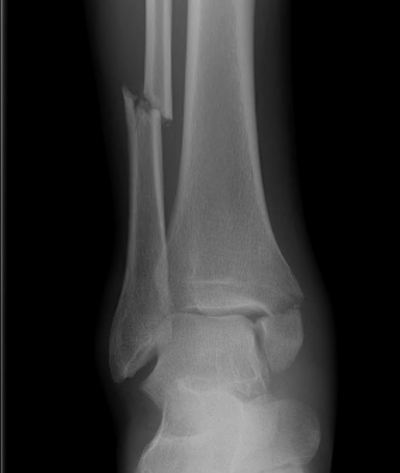

骨折圖片